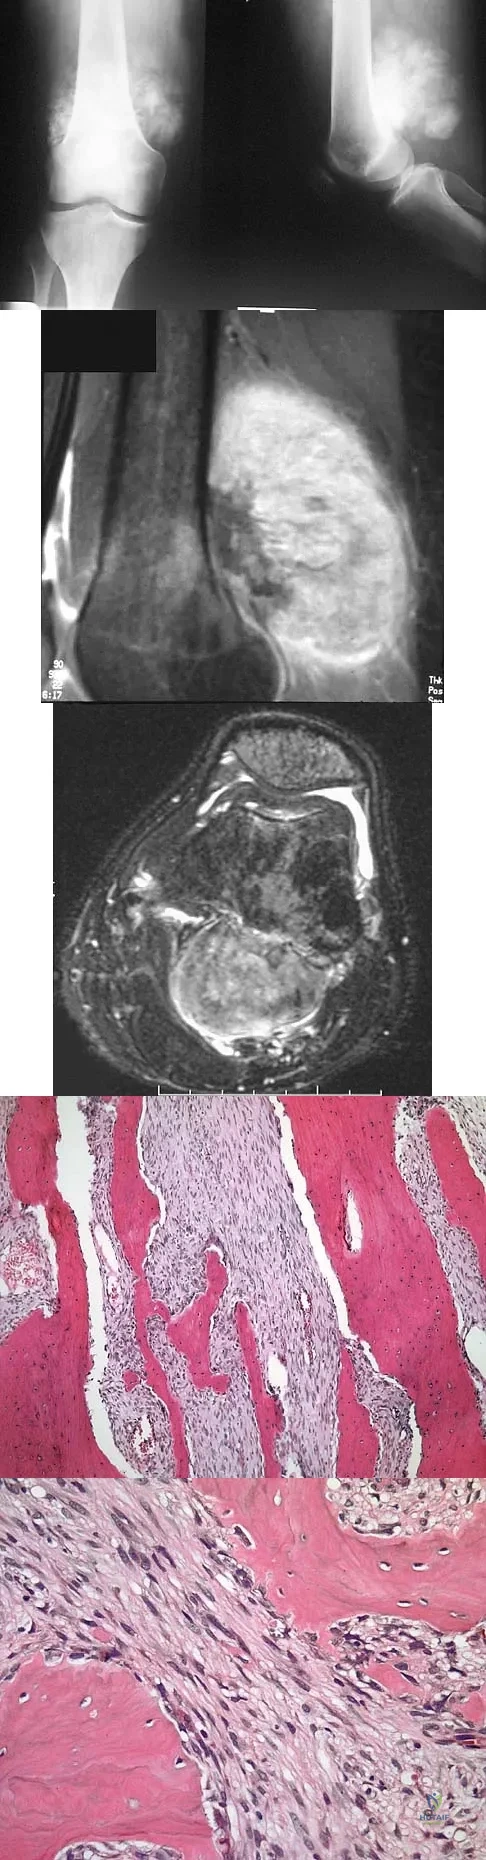

A 12-year-old girl has had increasing left knee pain for the past 3 months. A radiograph is shown in Figure 75a, and low- and high-power photomicrographs are shown in Figures 75b and 75c. What is the most appropriate treatment?

A 7-year-old girl has had a painful forearm for the past 2 months. Examination reveals fullness on the volar aspect of the forearm. Radiographs and an MRI scan are shown in Figures 42a through 42c. Biopsy specimens are shown in Figures 42d and 42e. What is the most likely diagnosis?